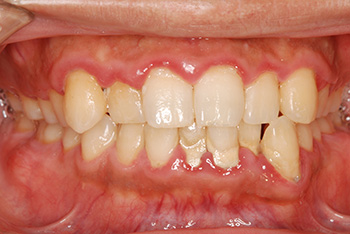

左:初診時。プラークが溜まりやすい不良な被せ物のせいで、歯肉が炎症を起こし赤く腫れています。

右:歯周治療が終了し被せ物を新しく作り直した後。赤く腫れていた歯肉は引き締まり、健康なピンク色に戻りました。